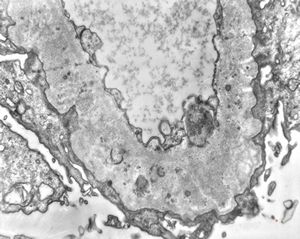

M,29y. | type II membranoproliferative glomerulonephritis (dense deposit disease)